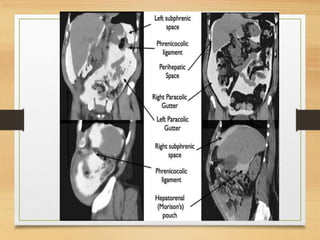

ESPACIOS PERITONEALES

El mesocolon transverso divide la cavidad peritoneal en 2 grandes compartimentos

1. Supramesocólico

• Espacios subfrénicos derecho e izquierdo

• Espacios perihepáticos derecho e izquierdo

• Espacio subhepático

• Espacio periesplénico

• Saco menor

2. Inframesocólico

• Gotieras paracólicas derecha e izquierda

• Espacio pélvico

• Porción central del abdomen

Espacios Supramesocolicos Izquierdos

• Los espacios supramesocólicos izquierdo y

derecho suelen comunicarse libremente entre

sí e incluyen los espacios perihepáticos,

subfrénicos izquierdo y perisplénico

Espacios Supramescolicos Derecho

• Los espacios supramesocólicos derechos

incluyen el espacio subfrénico derecho

(subdiafragmático), la bolsa Morison (espacio

subhepático o hepatorenal) y el saco menor

(bursa omental)

Espacios Inframescolicos

Derecho e Izquierdo

• El espacio inframesocólico

derecho más pequeño está

limitado inferiormente por la

unión del mesenterio del intestino

delgado al ciego. Las colecciones

aquí no se extienden

generalmente en la pelvis. Por

otro lado, el espacio

inframesocólico izquierdo más

grande comunica libremente con

la pelvis.

• ESPACIOS PARACÓLICOS (CANALONES)

Estos espacios se localizan lateralmente a las reflexiones peritoneales que

cubren el colon izquierdo y derecho. A la derecha el espacio se comunica con

los espacios supracolicos. A la izquierda, el ligamento frenocólico es un

impedimento relativo pero no completo para que los procesos patológicos se

trasladen de paracólica izquierdo al espacio subfrénico.